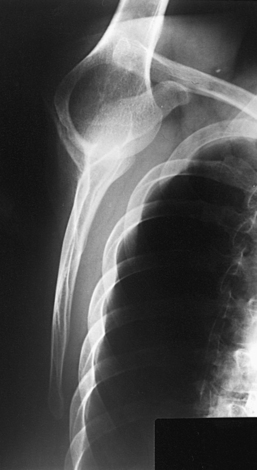

Structures shown: A lateral image of the shoulder and proximal humerus is projected through the thorax (Figs. 5-25 and 5-26).

Structures shown: The scapular Y is shown on an oblique image of the shoulder. In the normal shoulder, the humeral head is directly superimposed over the junction of the Y (Fig. 5-37). In anterior (subcoracoid) dislocations, the humeral head is beneath the coracoid process (Fig. 5-38); in posterior (subacromial) dislocations, it is projected beneath the acromion process. An AP shoulder projection is shown for comparison (Fig. 5-39).

Fig. 5-38 PA oblique shoulder joint showing anterior dislocation (humeral head projected beneath coracoid process).